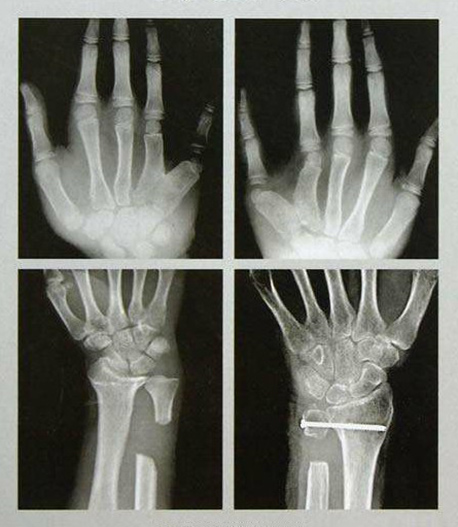

手足外科設(shè)有床位40張,舟山市醫(yī)學(xué)會(huì)手足外科專業(yè)委員會(huì)主任委員姜德欣主任醫(yī)師擔(dān)任學(xué)科帶頭人??剖姨峁┥舷轮褪肿悴康母鞣N骨折、外傷、感染、畸形、功能障礙的手術(shù)治療,復(fù)雜創(chuàng)傷性四肢的保肢、斷指(趾)再植手術(shù),及各種軟組織缺損的修復(fù)、周圍神經(jīng)損傷、血管損傷的治療及糖尿病足等的綜合治療。